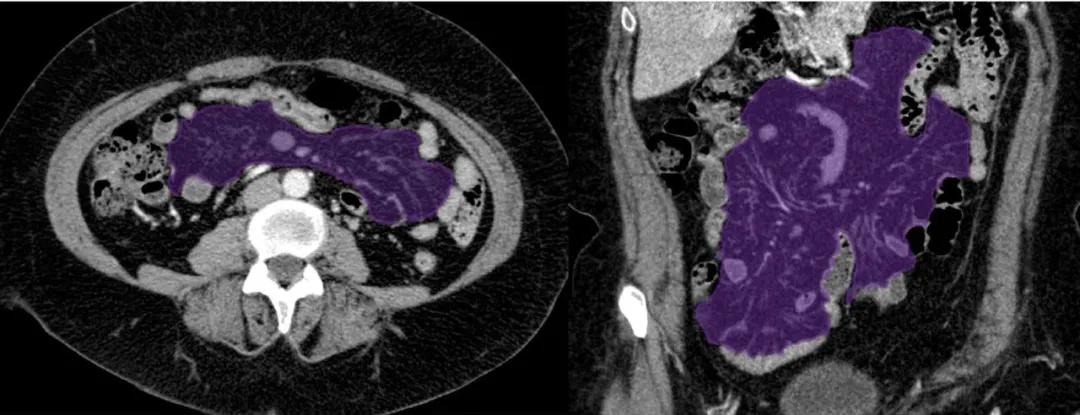

含肠系膜上动脉分支的小肠系膜(紫色)。